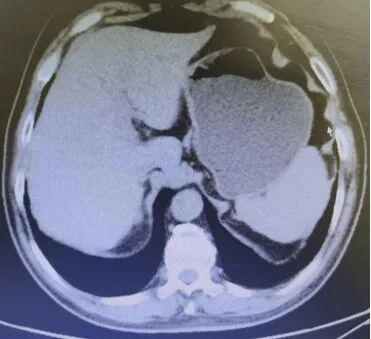

Abdominal CT films (2 sheets) on August 13, 2019